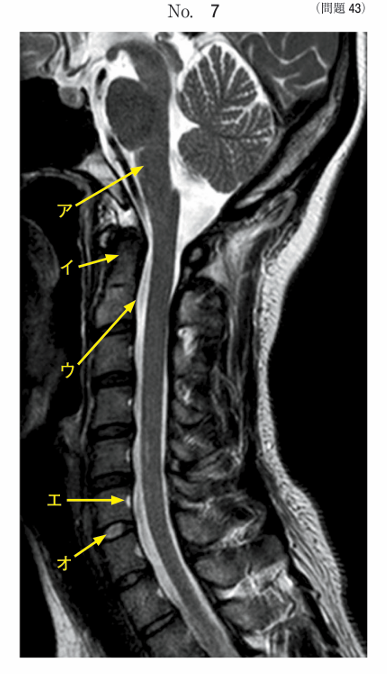

午前/問題43

頸部のMR像別冊No. 7を別に示す。正しいのはどれか。2つ選べ。

1.アは橋である。

2.イは隆椎である。

3.ウは頸髄である。

4.エは椎体静脈である。

5.オは髄核である。